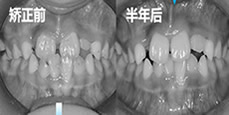

當(dāng)我地包天選擇用Damon金屬托槽做掩飾性正畸,結(jié)果...

地包天地包天矯正器發(fā)布時(shí)間: 2023-05-07

其實(shí)在矯正后才發(fā)現(xiàn),地包天除了做正頜手術(shù)外還有第二條路可以走,那就是做金屬的掩飾性正畸,并且花費(fèi)不會(huì)很高, 也就不到兩萬(wàn)元。